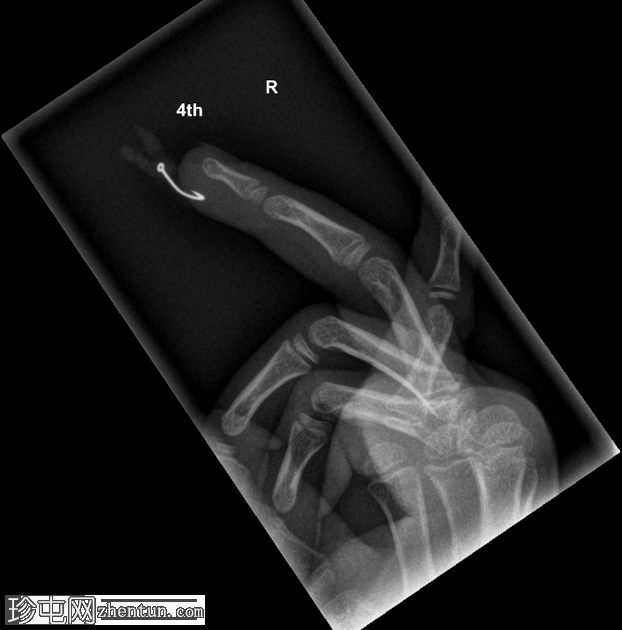

右手无名指

X光片

侧位片

鱼钩异物,附有蛆虫。

鱼钩异物较为常见,但像本例中鱼钩上还附着蛆虫的情况则较为罕见!